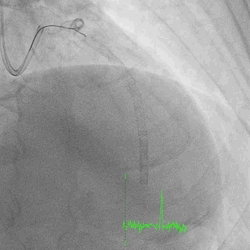

A 60-year-old man with type 2 diabetes, hypertension, and hyperlipidemia, as well as a history of coronary interventions with bare metal stenting for LCX and LAD, underwent drug-eluting ballooning for ISRs in both LCX and LAD in March 2019. Stent under-expansion at the proximal LAD was noted and he was then re-admitted this time for OCT-guided contrast-facilitated excimer laser therapy. Follow-up diagnostic angiogram revealed stent under-expansion at the proximal LAD, as shown in figures 1a and 1b. PCI was approached with XB 3.0 x7F guide via right radial access. Initially, the guide support was not sufficient and the 1.4 mm laser catheter could not go through the lesion, resulting in contrast leakage from the guide into the aorta (Figure 2a). Predilatation with a 2.5x8mm NC BC could not fully dilate the lesion, even up to 30 bars (figures 2b and 2c). A 7F Guidezilla was used to extend the guide catheter and the lesion was treated with excimer laser 6 times at 60 mJ/mm2, 40 Hz, with slow advancement of the laser catheter during activation and facilitated by 1:1 contrast: saline dilution (Figures 3a and 3b). With further BC dilatation, the lesion could be fully opened and finalized with drug-eluting BC treatment (Figure 4a and 4b). Pre- and post-PCI OCT showed disruption of the calcified ISR and full opening of the double-layered stent (figure 5). The patient was discharged from the hospital the next day and has remained completely asymptomatic ever since.

Figure 1a and 1b